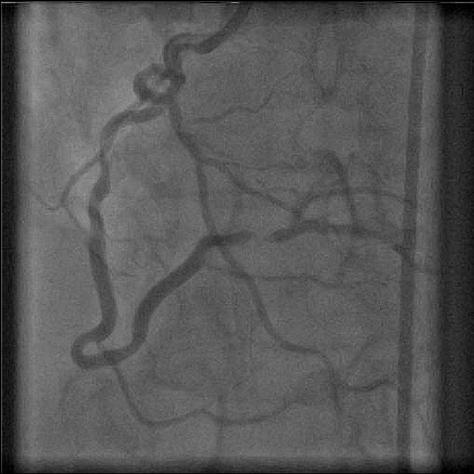

Right dominance: the posterior descending coronary artery is a branch of the right coronary artery (segment 4).